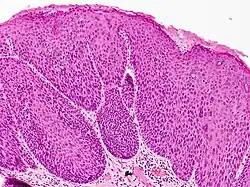

Pathologie

In der lichtmikroskopischen Untersuchung sieht man eine umschriebene Verbreiterung der Epidermis (Oberhaut) mit Hyper- und/oder Parakeratose (überschießende bzw. gestörte Verhornung). Die Schichtung der Epidermis ist aufgehoben und die Zellkerne der Keratinozyten (hornbildende Zellen der Oberhaut) variieren in Form, Größe und Chromatindichte. Als Zeichen der unkontrollierten Zellteilung findet man Mitosen (Kernteilungsfiguren) in der gesamten Epithelbreite sowie Dyskeratosen (vorzeitig verhornte Keratinozyten). Besonders in den oberflächlichen Anteilen der Epidermis kann sich eine HPV-typische Koilozytose (zytoplasmatische Hofbildung um den Zellkern) zeigen.[11][7]

In der immunhistochemischen Färbung auf p16 färben sich Zellkerne und Zytoplasma der Keratinozyten in der gesamten Breite der Epidermis kräftig an.[12]